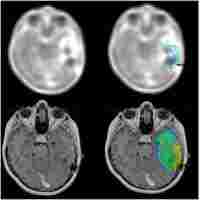

| Abstract | Neuroimaging based on O-(2-[18F]fluoroethyl)-L-tyrosine (FET)-PET provides additional information on tumor grade and extent compared to MRI. Dynamic PET for biopsy target selection further improves results but is often clinically impractical. Static FET-PET performed at two time-points may be a good compromise, but data on this approach are limited. The aim of this study was to compare the histology of lesions obtained from two challenging glioma patients with targets selected based on hybrid dual time-point FET-PET/MRI. Five neuronavigated tumor biopsies were performed in two difficult cases of suspected glioma. Lesions with (T1-CE) and without contrast enhancement (T1 and T2-FLAIR) on MRI were selected. Dual time-point FET-PET imaging was performed 5-15 minutes (PET10) and 45-60 minutes (PET60) after radionuclide injection. The most informative FET-PET/MRI images were co-registered with MRI in time of biopsy planning. Five biopsy targets (three from high uptake and two from moderate uptake FET areas) thought to represent the most malignant sites and tumor extent were selected. Histopathological findings were compared with FET-PET and MRI images. Increased FET uptake in the area of non-CE locations on MRI correlated well with high grade gliomas localized as far as 3 cm from T1-CE foci. Selecting a target in the motor cortex based on FET kinetics defined by dual time-point PET resulted in a grade IV diagnosis after previous negative biopsies based on MRI. An additional grade III diagnosis was obtained from an area of glioma infiltration with moderate FET uptake (between 1-1.25 SUV). This findings seem to show that dual time-point FET-PET-based biopsies can provide additional and clinically useful information for glioma diagnosis. Selection of targets based on dual time-point images may be useful for determining the most malignant tumor areas and may therefore be useful for resection and radiotherapy planning. |